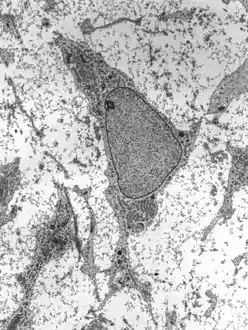

خلية جذعية

الخلايا الجذعية - وتُسمّى أيضًا الخلايا الجذرية[2] (بالإنجليزية: Stem Cells) هي خلايا غير متخصصة ولكن يمكنها أن تتمايز إلى خلايا متخصصة، مع تميزها بقدرتها على الانقسام لتجدد نفسها باستمرار.[3]